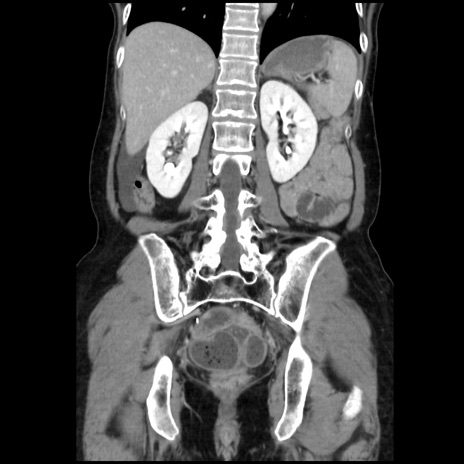

症例32(冠状断像)

【症例】40歳代 女性

【主訴】上腹部痛、嘔気・嘔吐

【現病歴】約9時間前頃から急に上腹部痛、嘔気、嘔吐が出現。改善しないため救急要請。

【既往歴】子宮頚癌(広汎子宮全摘術、放射線療法)、腸閉塞

【身体所見】腹部:平坦、軟、腸雑音亢進、上腹部を中心に腹部全体に圧痛あり。

【データ】WBC 8400、CRP 0.03